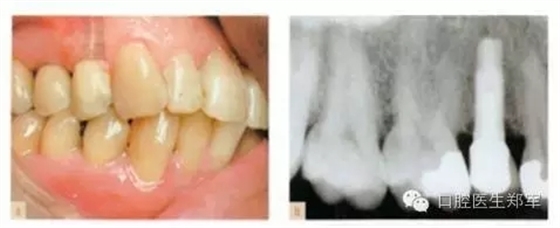

單顆牙缺失的種植體修復(fù):與自然牙齒修復(fù)相似,都是由咬合原則指導(dǎo)。種植體中心咬合接觸,咬合面減徑(如果可能的話),牙尖平坦(如果可能的話),全牙列在最大牙尖交錯時能夠同時接觸,以上這些都具備臨床和生物力學(xué)意義。修復(fù)體不應(yīng)該有非正中干擾,但是適當(dāng)?shù)臅r候可以設(shè)計(jì)成部分選擇性非正中引導(dǎo)。(圖1和圖2)

圖1 a-b 單顆前磨牙種植、良好的接觸、同時全口咬合接觸、以種植體中心為咬合接觸點(diǎn)。 |